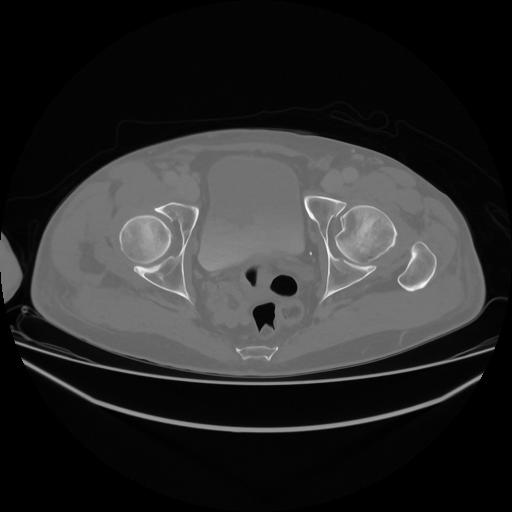

5 CUERPO,CE,Vol,1.0,CUERPO,,